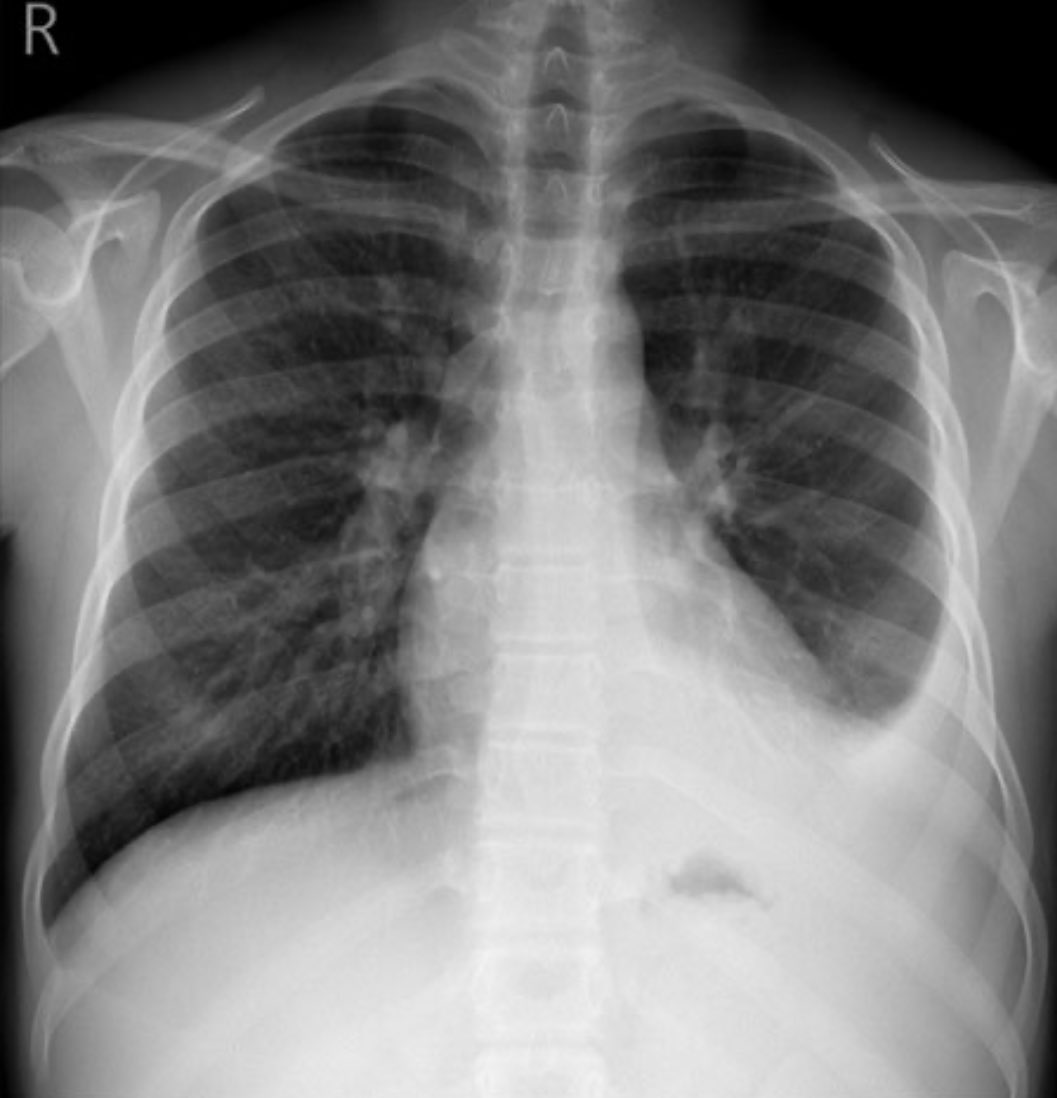

A 20yo male came to the ER with fever, chills and shortness of breath. A chest X-ray was done. 🚑 What is the name of the sign you see? What does it classically indicate?

A 20yo male came to the ER with fever, chills and shortness of breath. A chest X-ray was done. 🚑

What is the name of the sign you see?

What does it classically indicate?